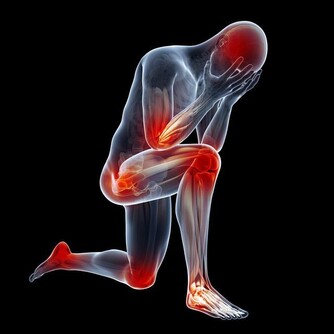

氣毒氣毒是存在肺裡面的毒,中醫認為“肺主氣”、“腎主納氣”,有氣毒的人往往肺腎功能不好,一般身上氣味大,如有口臭、汗臭等。為了防止氣毒,可以每天早起做深呼吸,即“呼吸吐納”,把肺中的濁氣排出來,保持體內空氣的新鮮。